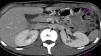

El estudio de angiotomografía del riñón y los vasos arteriales y venosos mostró un aumento en el diámetro de la vena renal izquierda en su porción distal (fig. 1). No se observaron datos indirectos de obstrucción en la segunda porción del duodeno.

Los hallazgos del estudio de angiotomografía no fueron concluyentes pues, aunque se observó aumento del diámetro de la vena renal izquierda en su porción distal, los intentos para validar el diámetro normal de la vena renal izquierda en su porción distal no han sido exitosos debido a que la dilatación de la vena renal izquierda puede ser una variante normal1.